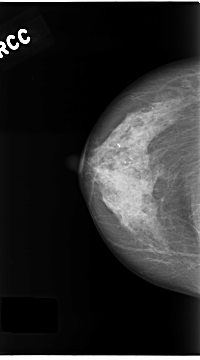

C_0180_1.RIGHT_MLO

C_0180_1.RIGHT_CC

RIGHT_CC LINES 4680 PIXELS_PER_LINE 2600 BITS_PER_PIXEL 12 RESOLUTION 50 NON_OVERLAY

RIGHT_MLO LINES 4688 PIXELS_PER_LINE 2520 BITS_PER_PIXEL 12 RESOLUTION 50 NON_OVERLAY